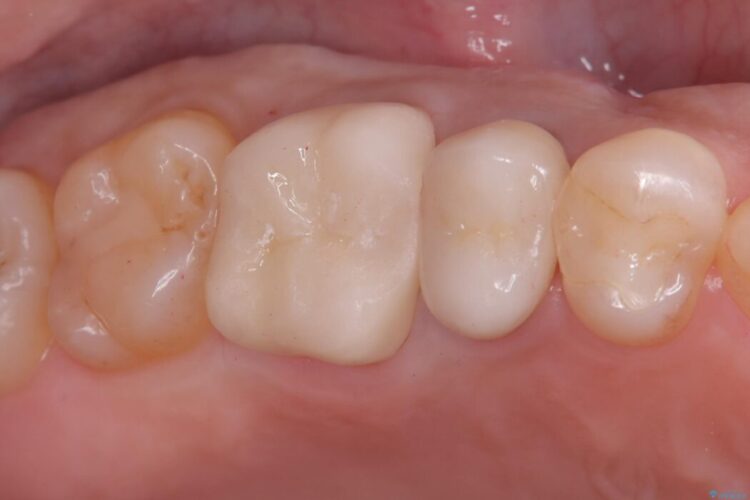

その後、残りの歯を保護して強度を上げるため、適合性が高いオールセラミッククラウンの作成・装着を行いました。

セラミッククラウンは、

強度: 歯全体を覆うため、咬合力による歯への負担を分散させ、破折リスクを大幅に軽減します。

審美性: 天然歯に近い透明感と色調を持つため、銀歯の時と比べて格段に自然で美しい見た目になります。